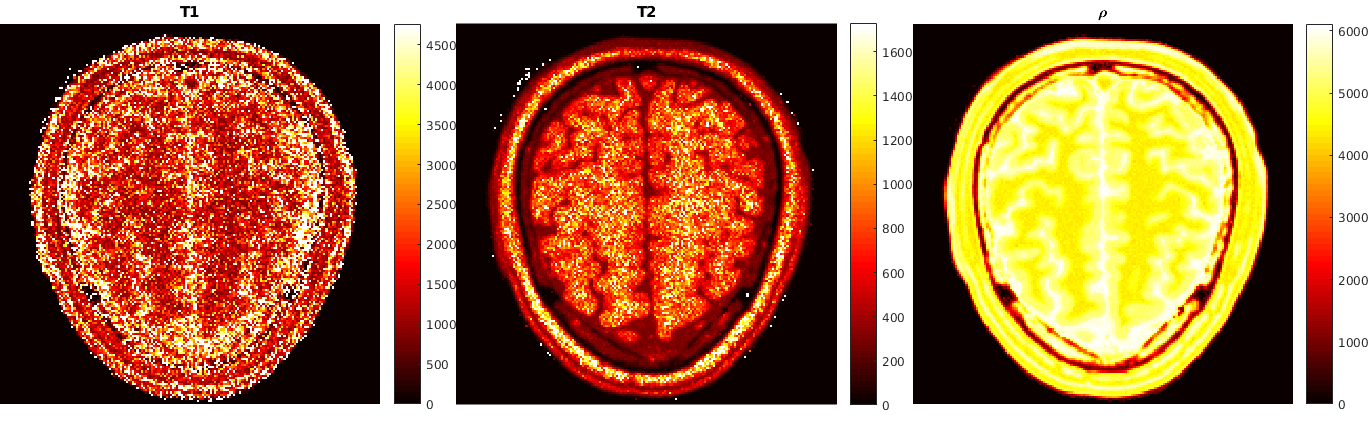

The second example comes from quantitative magnetic resonance imaging - qMRI. In this context, one integrates a mathematical model of the acquisition physics (the Bloch equations [16]) into the associated image reconstruction task in order to relate qualitative information (such as the net magnetization y=ρm𝑦𝜌𝑚y=\rho m) with objective, tissue dependent quantitative information (such as T1subscript𝑇1T_{1} and T2subscript𝑇2T_{2}, the longitudinal and the transverse relaxation times, respectively, or the proton spin density ρ𝜌\rho). This model is then used to obtain quantitative reconstructions from subsampled measurement data g𝑔g in k-space by a variational approach. The provision of such quantitative reconstructions is highly important, e.g., for subsequent automated image classification procedures to identify tissue anomalies. Moreover, in [16] it is demonstrated that such an integrated physics-based approach is superior to the state-of-the-art technique of magnetic resonance fingerprinting (MRF) [32] and its improved variants [14, 34]. Specifically in MRI, acquisition data are obtained at different pre-specified times (read-out times) t1,,tLsubscript𝑡1subscript𝑡𝐿t_{1},\ldots,t_{L}, during which the magnetization of the matter is excited through the control of a time dependent external magnetic field B𝐵B. Given u=(T1,T2,ρ)𝑢subscript𝑇1subscript𝑇2𝜌u=(T_{1},T_{2},\rho), the magnetization time vector at t1,tLsubscript𝑡1subscript𝑡𝐿t_{1},\ldots t_{L} is then given by y=Π(u)𝑦Π𝑢y=\Pi(u), where ΠΠ\Pi denotes the solution map associated with a discrete version of the Bloch equations. Crucial to this approach is the fact that, at least for specific variations of the external magnetic field B𝐵B, explicit formulas for the solution map of the Bloch equations are available. For instance, in [14] and [16] Inversion Recovery balanced Steady-State Free Precession (IR-bSSFP) [41] is used which involves certain flip angle sequence patterns that characterize the external magnetic field B𝐵B. These flip angle patterns allow for a simple approximation of the solutions of the Bloch equations at the read-out times through a recurrence formula. However, in general, it is quite typical that for more complicated external magnetic fields one does not have at hand explicit representations for the Bloch solution map. More generally, for most nonlinear differential equations (including those relevant in image reconstruction tasks) explicit solution maps might be too complicated to obtain. However, one may employ numerical methods to approximate their solutions (yi)i=1nDsuperscriptsubscriptsubscript𝑦𝑖𝑖1subscript𝑛𝐷(y_{i})_{i=1}^{{n_{D}}} given a specific (coarse) selection of parameters (ui)i=1nDsuperscriptsubscriptsubscript𝑢𝑖𝑖1subscript𝑛𝐷(u_{i})_{i=1}^{{n_{D}}} within a certain range. This generates a data set D𝐷D which is then employed in a learning procedure to generate an ANN based approximation Π𝒩subscriptΠ𝒩\Pi_{\mathcal{N}} of ΠΠ\Pi. This gives rise to Q𝒩:=AΠ𝒩assignsubscript𝑄𝒩𝐴subscriptΠ𝒩Q_{\mathcal{N}}:=A\Pi_{\mathcal{N}} in (1.2) and requires an associated analytical as well as numerical treatment of the (reduced) minimization problem.